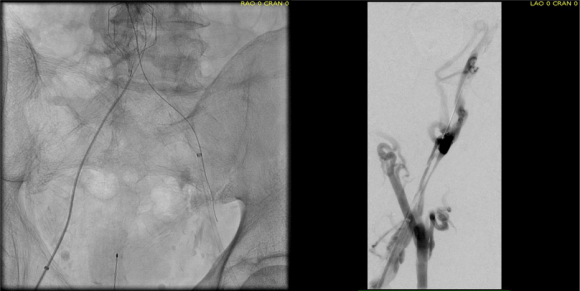

intervention fig 1.png

Advancing wire and sheath into iliac vein, crossing filter resulted in extravasation of contrast

Once position confirmed to be in the iliac vein, the vein was dilated to allow for greater ease of movement. In the case of the uncrossable filter, I switched to access from above via a right internal jugular vein access.

intervention fig 2.png

Dilating vein (left) for greater mobility, and crossing from above (R. IJV access)